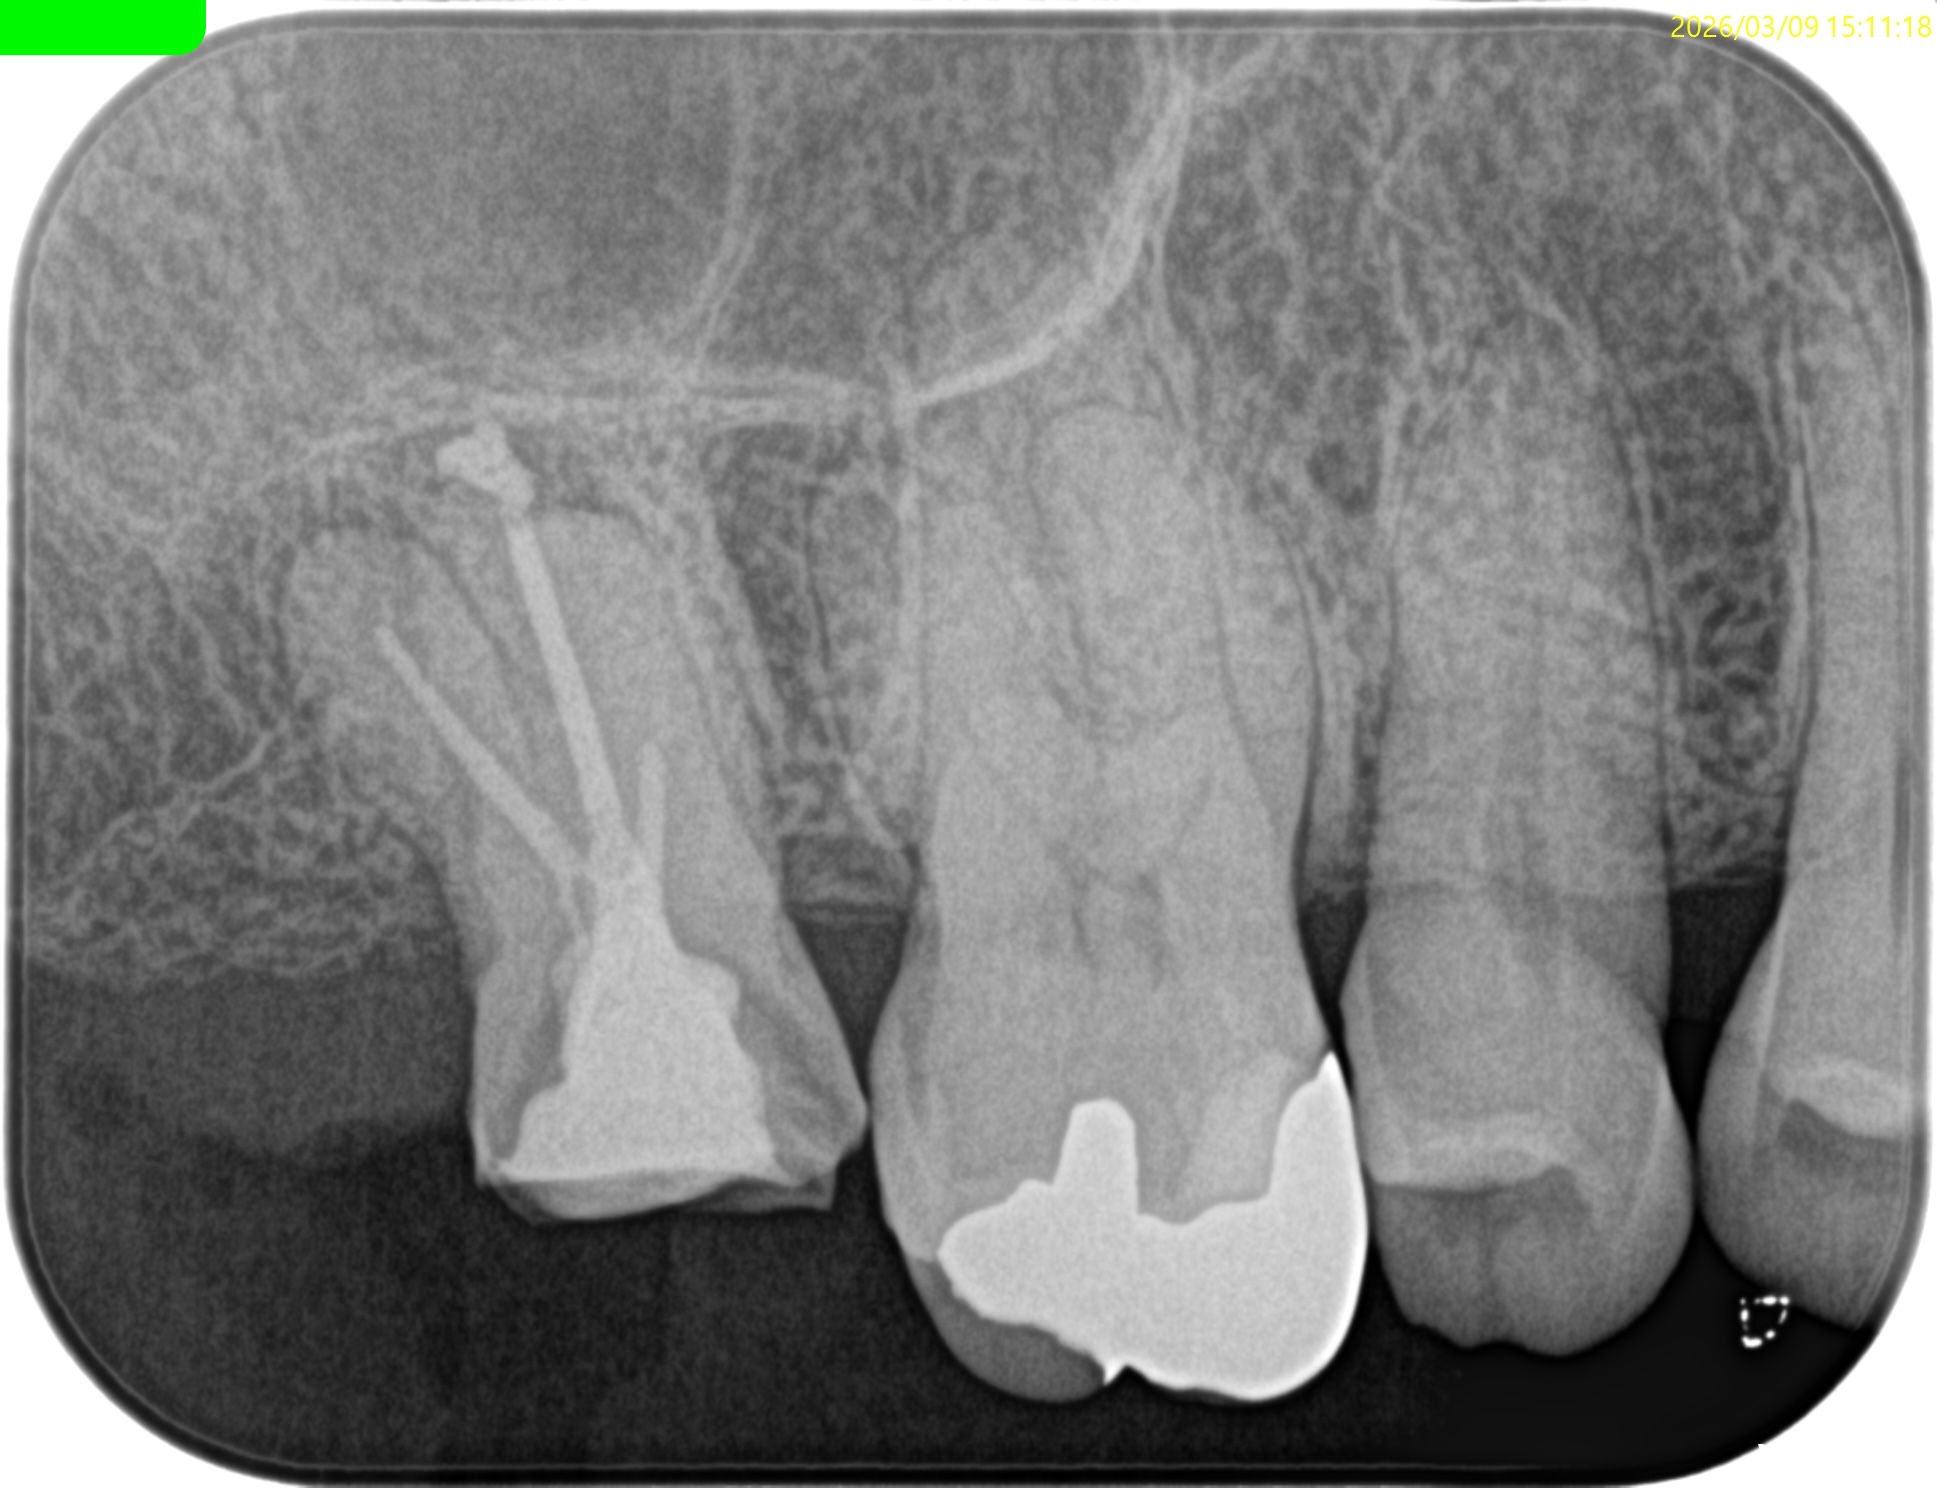

根管充填後にPA, CBCTを撮影した。

DB

P

問題はないだろう。

次回は半年後である。